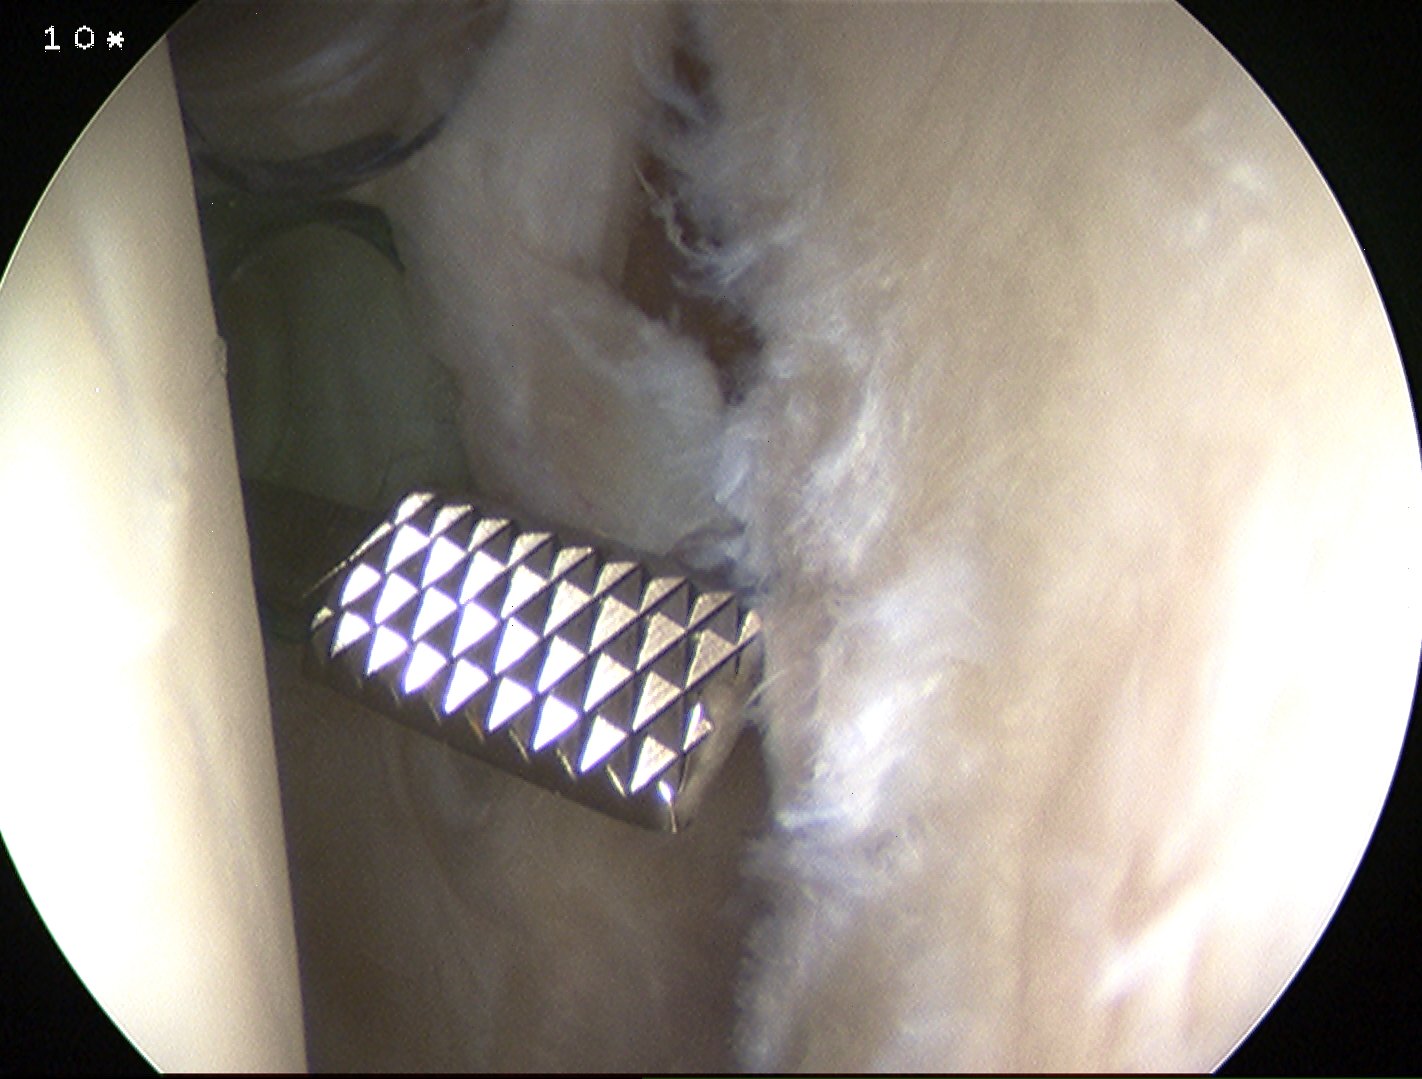

Hill Sachs lesion

Remplissage

- RCT of 100 patients with <15% glenoid bone loss

- arthroscopic Bankart v Bankart + Remplissage

- Bankart only: recurrent instability 18%

- Bankart + Remplissage: recurrent instability 4%